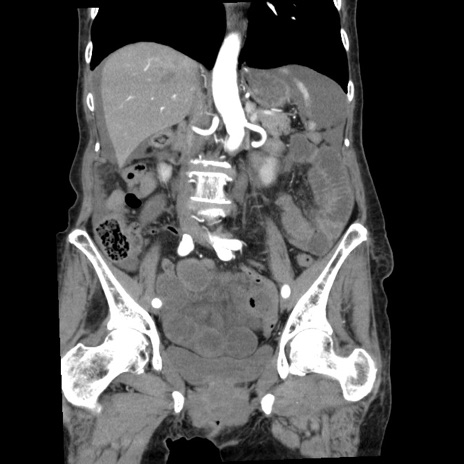

横断像

【症例】80歳代女性

【主訴】腹痛

【現病歴】8時間前から腹痛あり来院。

【既往歴】糖尿病、脂質異常症、子宮体癌にて子宮全摘術

【身体所見】意識清明・会話良好だが腹痛で苦悶様、全腹部にわたって反跳痛と圧痛あり

【データ】WBC 13600、CRP 0.14、LDH 224、CK 90